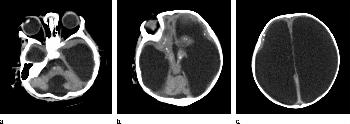

Figure 3. Images obtained in the case of a 34-year-old woman with confirmed Zika virus infection, initially seen for a rash at 8 weeks of gestation. Fetal head cir¬cumference was in the normal range at 12 and 16 weeks (5.8 cm and 11.9 cm, respectively) but then decreased to the 10th percentile at 22 weeks and was below the 3rd percentile in subsequent imaging examinations. (a–h) US images were obtained at 30 weeks. Head circumference on the axial image (a) measured 24 cm (˂2.3 percentile, corresponding to a gestational age of 26 weeks 3 days). Note the open sylvian fissures and relatively smooth cortex, which are abnormal findings at this gestational age. Oblique axial image (b) shows cerebellar calcifications (seen as the echogenic outer contour of the cerebellar hemispheres) and inferior vermian hypoplasia with associated enlarged cisterna magna. A sagittal transvaginal image (c) shows calcifications in the basal ganglia (arrowheads) and more bulky calcifi¬cation at the gray matter–white matter junction. Another sagittal transvaginal image (d) shows a relatively small corpus callosum (arrows). A coronal image (e) shows cortical and subcortical white matter calcifications in a linear pattern. The gyral pattern is abnormal, which is suggestive of polymicrogyria. A sagittal Color Doppler image (f) shows a stretched appearance of vessels coursing into the posterior fossa. An oblique axial grayscale transvaginal image in the posterior fossa (g) shows heterogeneous material in the confluence of sinuses due to blood clot (arrow). A three-dimensional US image of the face (h) shows a sloping forehead, compatible with frontal lobe hypoplasia. (i) Axial and (j) sagittal fetal MR images obtained at 29 weeks show atrophic frontal lobes, wide sylvian fissures, enlarged posterior fossa, abnormal gyral pattern, prominent cerebrospinal fluid spaces, and inferior vermian hypoplasia. On (i), note the diffuse hypointense and undersulcated cortex, which is suggestive of mineralization and polymicrogyria. The hypoplastic corpus callosum can be seen on the sagittal view (j), as well as the inferior vermian hypoplasia, en¬larged cisterna magna, and heterogeneous signal intensity in the confluence of sinuses. There is a subjectively thin spinal cord. (k) Postnatal axial MR image obtained at 81 days shows small frontal lobes and cortical thickening. The choroid plexi are enlarged. (l) Photograph of the neonate after birth.

High-res (TIF) version